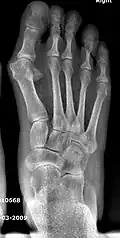

Primus varus deformity

Primus varus deformity is the leaning of the first metatarsal bone away from the second metatarsal and towards the opposite foot (Fig. 1). As it leans over, its head sticks out to form the bunion bump and it also widens the forefoot to cause shoes feeling too tight. Thus when bunion pain becomes unmanageable, surgical correction is to narrow the forefoot by repositioning of the first metatarsal head back to its normal position. This can be done by osteotomy (bone-breaking), soft tissue (non-osteotomy) or fusion techniques.

Syndesmosis procedure addresses specifically the two fundamental problems of metatarsus primus varus deformity that gives rise to the bunion deformity. They are leaning and instability of the first metatarsal bone . Syndesmosis procedure uprights the leaning first metatarsal bone with strong binding sutures between it and the second metatarsal bone (Fig. 2) and then also stabilizes it uniquely by creating a fibrous connecting bridge between these two bones (Fig. 3, 4). First metatarsal bone can be readily realigned because by definition of the metatarsus primus varus deformity its first metatarsal is abnormally loose and mobile.